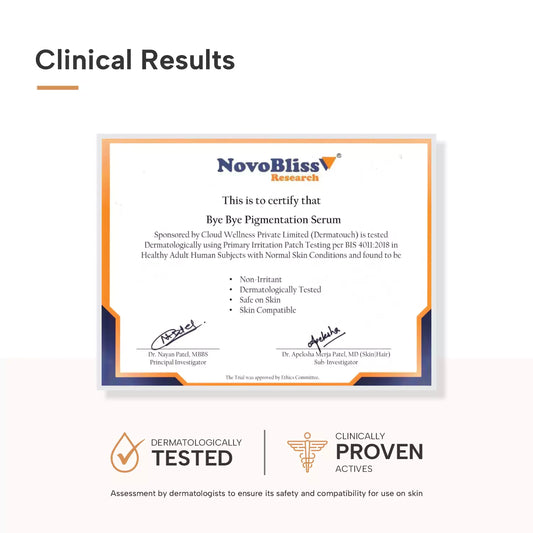

Bye Bye Pigmentation Serum 30ml

Dark Spots & Pigmentation

Bye Bye Pigmentation Serum 30ml

Dark Spots & Pigmentation